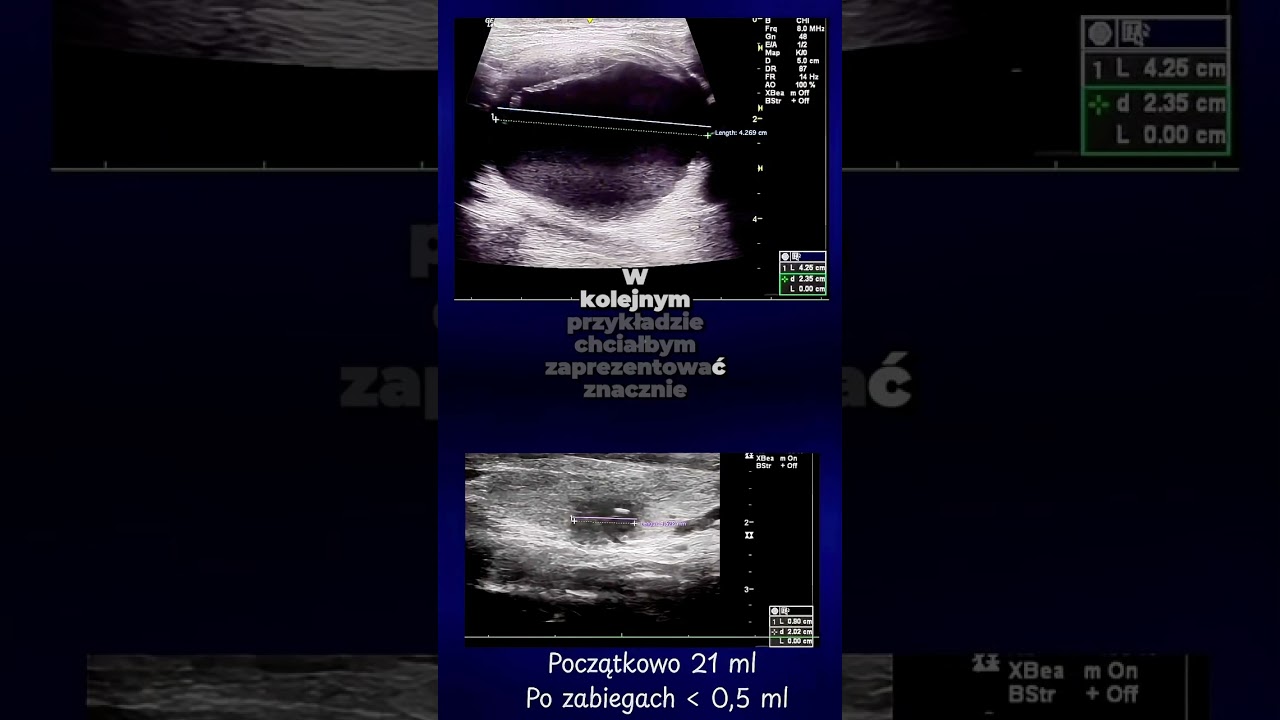

Wykonuję zabiegi leczenia guzków tarczycy małoinwazyjnymi metodami: laserowej termoablacji (EchoLaser) i przezskórnego leczenia etanolem.

Zapraszam do zapoznania się z relacją filmową z zabiegu leczenia etanolem guzka płynowego tarczycy wraz z opisem metody i wyjaśnieniami. Zabieg został przeprowadzony w Szpitalu na Klinach.